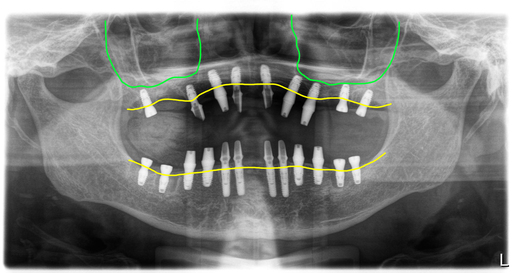

수술 상악 9개, 하악 12개 식립

드디어 수술하는 날이 되었습니다. 보철을 제거하고 상태가 좋지 않은 치아들은 모두 제거하고 남아있는 뼈를 최대한 이용해서 뼈이식과 함께 임플란트를 식립했습니다.

위 9개, 아래 12개 식립을 했고 위에는 6개 아래는 8개에 지대주를 연결해서 수술당일 임시치아를 적용해서 즉시하중 전체임플란트 치료를 했습니다.

고경이 낮아져 있었고,

그래서 상악과 하악관계가 좋지 않았습니다. 수술후 이 부분을 해소하기 위해 임시치아 적용시 고경을 조절해 드렸습니다.